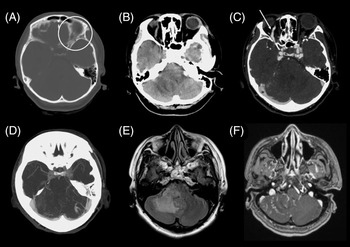

The CT head revealed an area of hypodensity in the right cerebellum and cerebellar peduncle with mass effect and effacement of the fourth ventricle (Figure 1B). CT angiography suggested a right dCCF with arterialization and fullness of the cavernous sinuses bilaterally. Both superior ophthalmic veins (SOVs) were dilated. There was arterialization of the right petrosal sinuses with cortical venous reflux resulting in numerous abnormally dilated and serpiginous vessels in the right cerebellum.

Figure 1: (A–D) CT and (E–F) MR head imaging demonstrates bilateral carotid-cavernous fistulas (CCFs) prior to endovascular intervention. (A) Left orbital and anterior cranial fossa fractures were sustained from a motor vehicle collision six weeks prior to the presentation. (B, E) Edema is noted in the right cerebellum and cerebellar peduncle on CT and MRI, suggestive of congestion. (C) Bilateral direct CCFs were visualized on CT angiography with engorgement of the right (white arrow) and left (not included on slice) superior ophthalmic veins (SOV). (D) Engorgement of bilateral cavernous sinuses and (D, F) distended cerebellar veins are seen on CT and MR angiography.